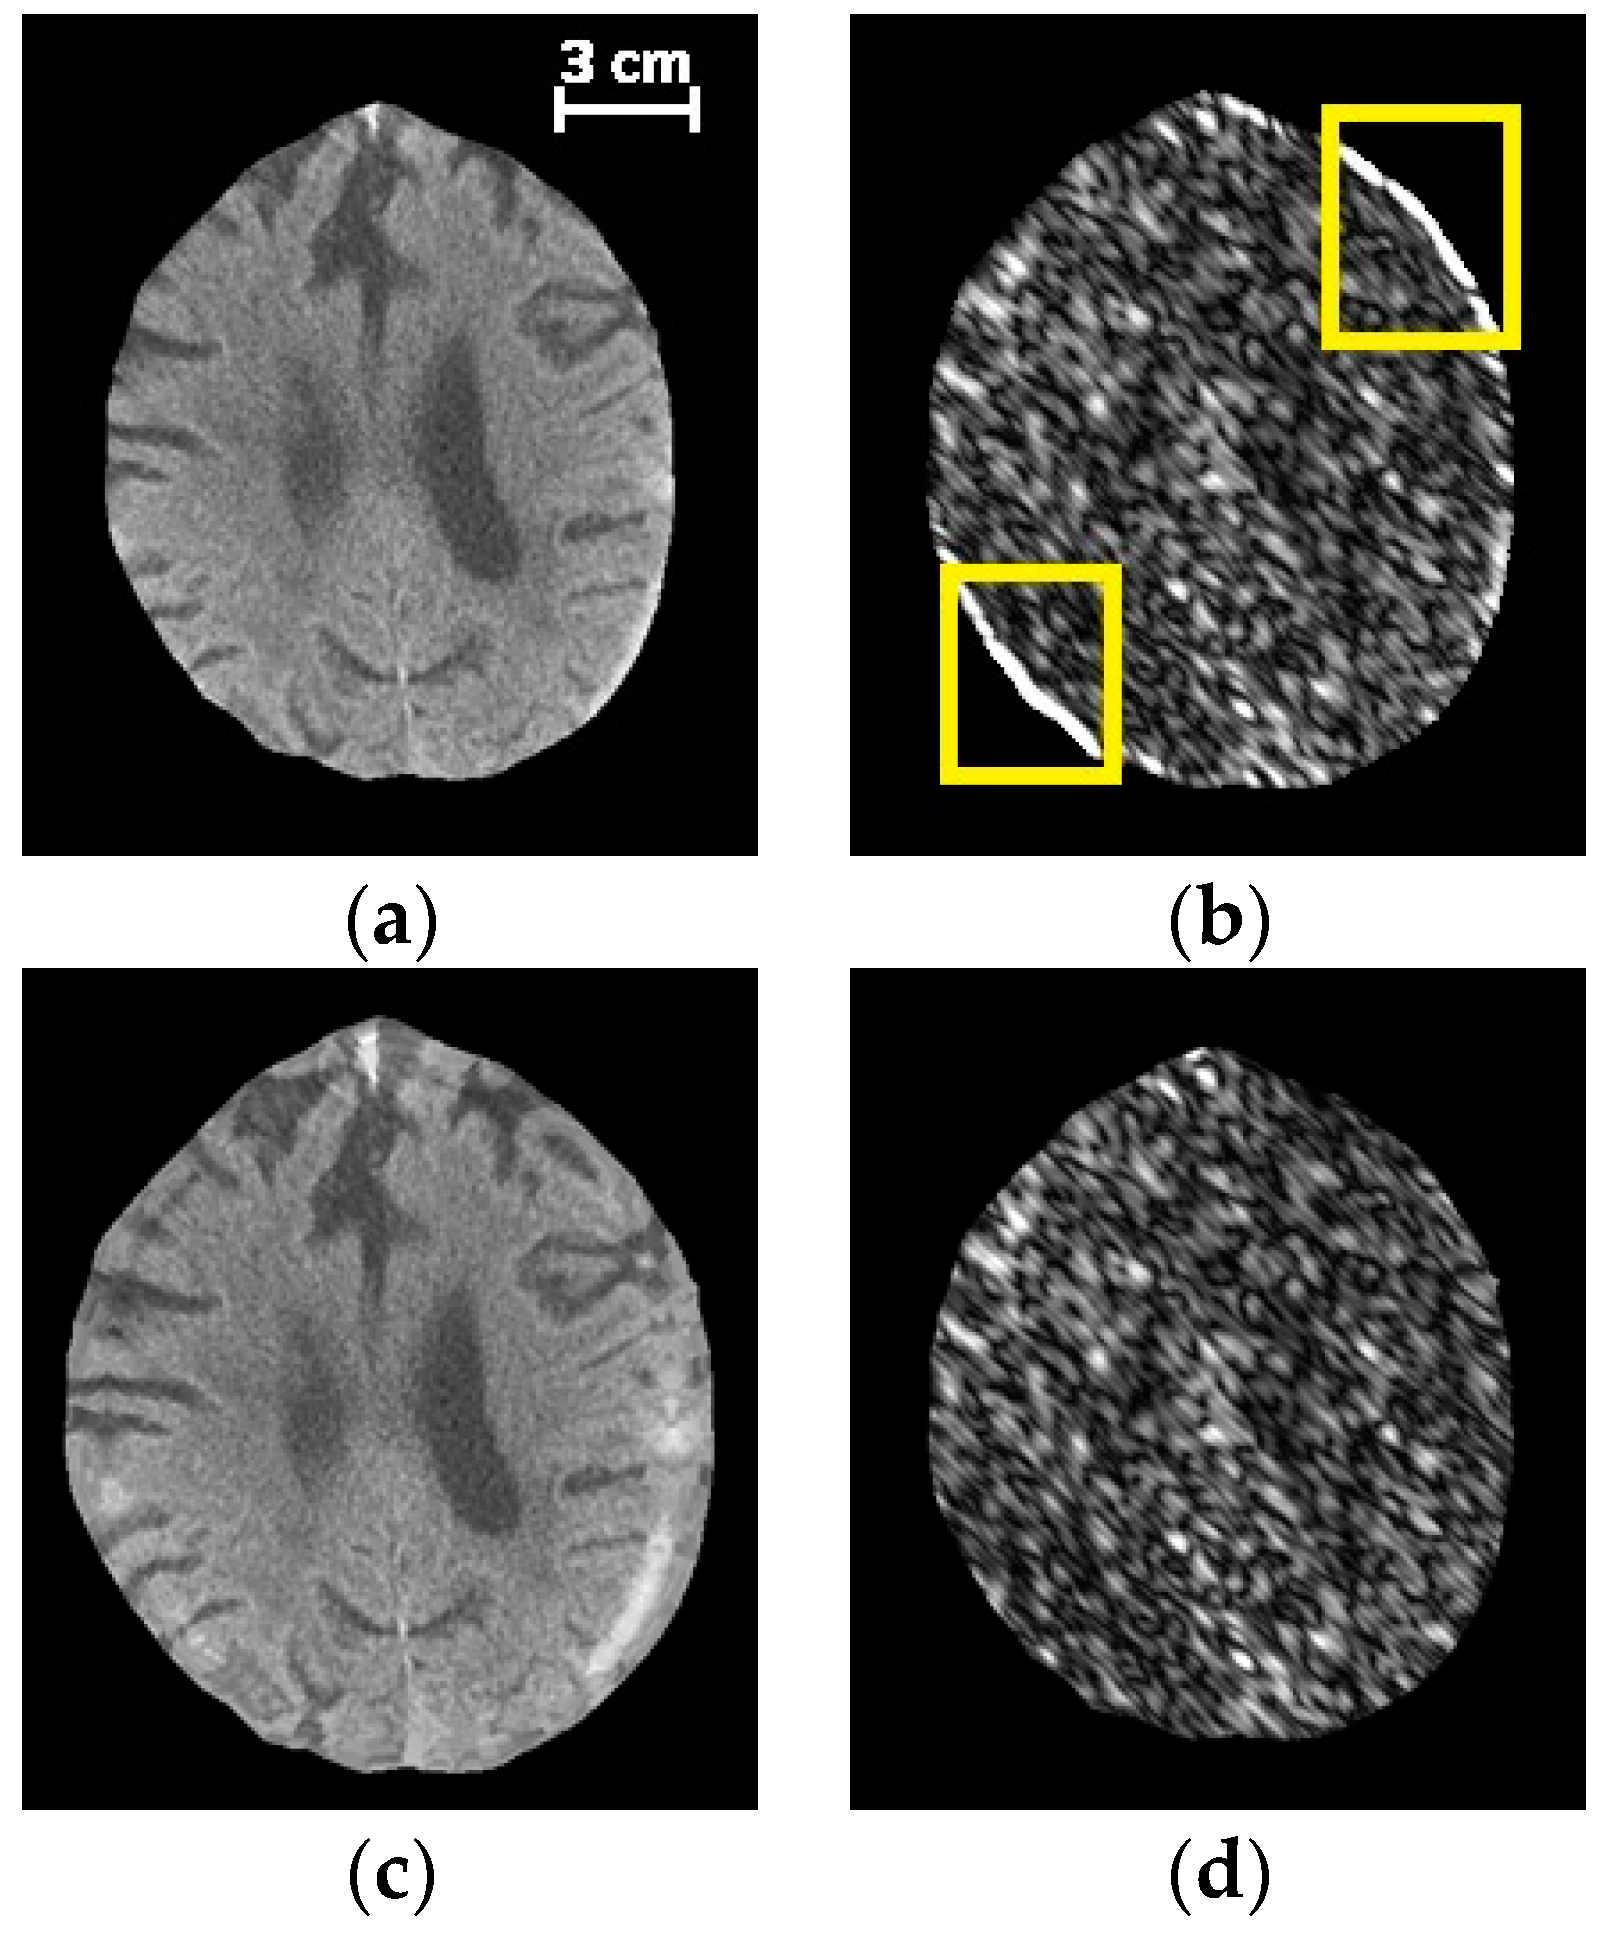

Histogram and filter analyses were performed to extract hand-crafted local textural information from the images. In order to derive local appearance information, a window with a fixed size of 25 × 25 pixels was localized around the center of each superpixel from which the corresponding features were derived. However, if the window was centered on superpixels close to the skull, where SDH tends to occur, the selected window would include pixels from skull. Thus, extracted textural features from the window would be affected by skull pixels and might not correctly represent SDH characteristics. For example, features that normally represent the orientation of brain/hematoma texture, would instead represent the skull orientation, which is not informative. Since SDH tends to occur adjacent to the skull, extracting correct features in this region is especially important for our purposes. In order to deal with this challenge, we removed the skull from the image and padded the image with a symmetric mirror reflection across the inner surface of the skull. As the boundary of the brain is not a straight line, we could not employ standard padding techniques. Instead, we proposed to iteratively pad the image across the irregular border of the intracranial region. This task was performed by maintaining two masks: the inner mask that shrank in each iteration and the outer mask that grew in each iteration. The region grown during each iteration was filled using the nearest pixel on the inner mask.

Figure 3 illustrates the intracranial region before and after padding, as well as the corresponding filtered image by applying a Gabor filter. The used Gabor filter highlights the textural component in the

orientation. In

Figure 3b, though there is no significant textural component in the

orientations, the filter enhances the border incorrectly within the region enclosed in yellow. As shown in

Figure 3d, this issue was resolved using the proposed padding method.